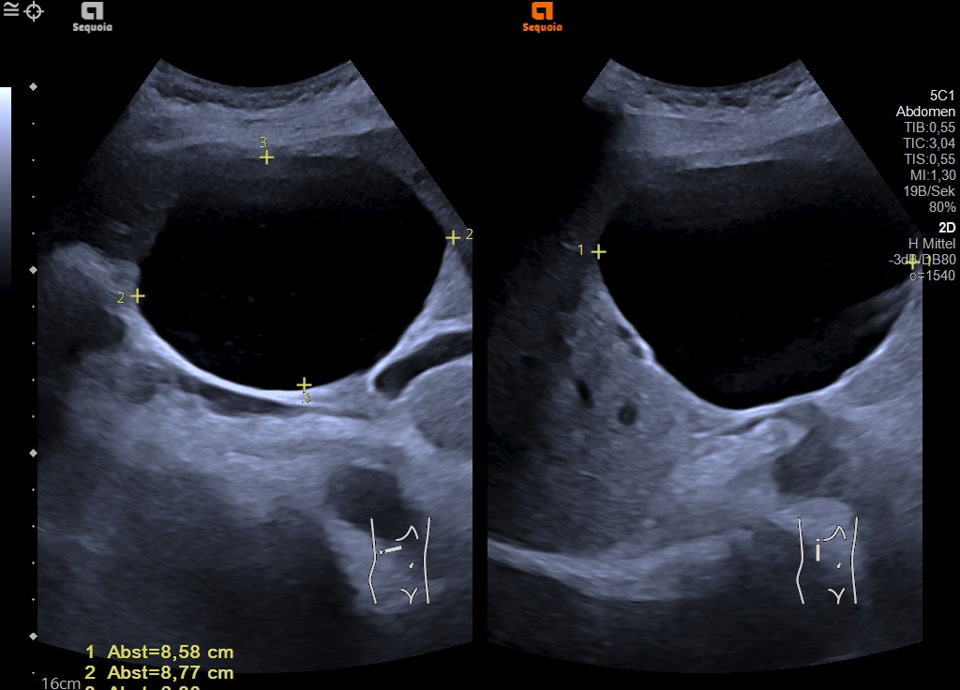

Simple cyst

• Simple liver cyst

• Simple liver cyst (2d-image)